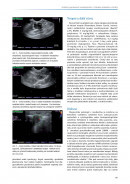

26 27

28 29

30 31

32 33

34 35

36 37

38 39